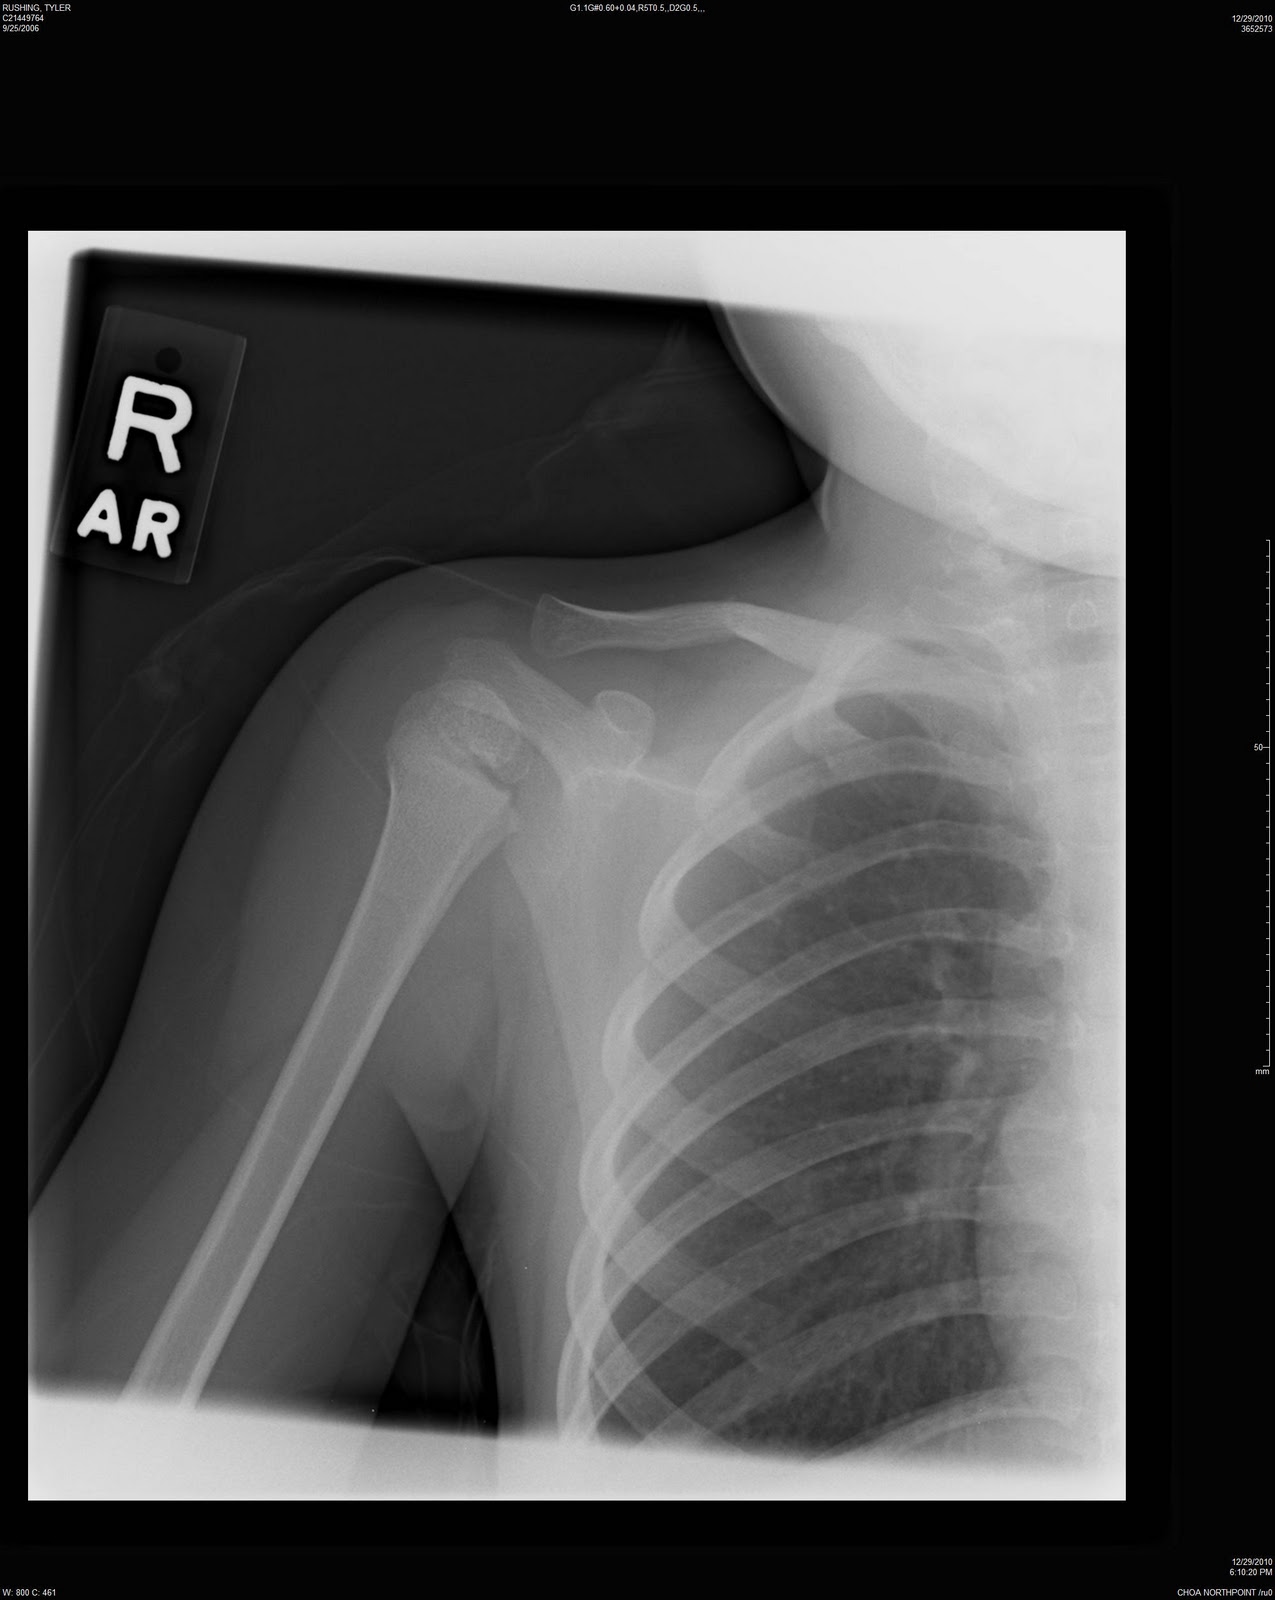

Broken Collarbone X-Ray . The clavicle is the most proximal bone of the upper. If the bone isn't too out of place and didn't break through the skin, you might be treated with a sling and limited. The two slender bones that start from the top of your sternum and extend. Symptoms of a broken collarbone include severe pain and swelling at the site of the fracture and with visible. To help pinpoint the location of the fracture; Clavicle fractures result in inferior displacement of the distal component. A broken collarbone is a fracture in one of your clavicles: Bone healing usually takes 3 to 6 weeks for children. People who have a broken collarbone usually need to wear a sling. To learn more about the severity of the break; The clavicle (collarbone) is one of the most fractured bones in the body.

Collarbone Injury Fort Wayne Slip & Fall Attorneys